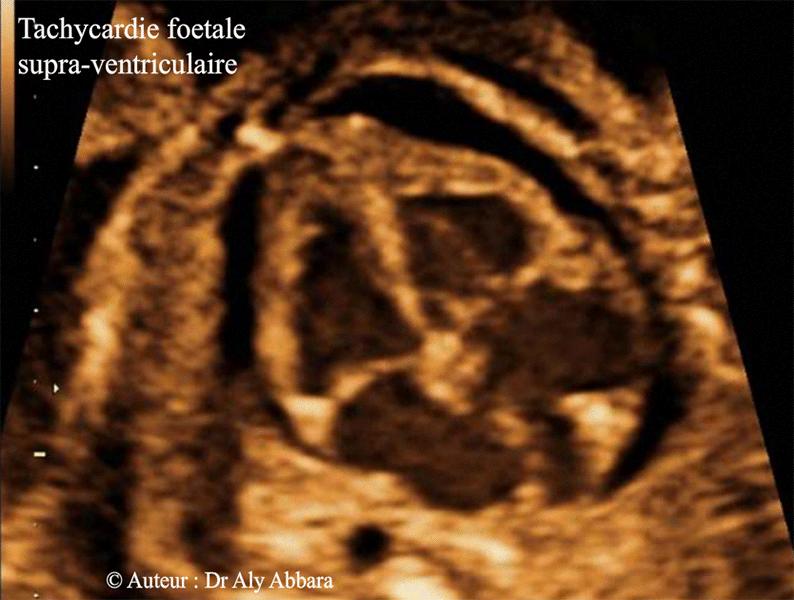

Tachycardie compliquée d'un épenchement péricardique faisant partie d'une anasarque foetoplacentaire - Grossesse de 23 SA

• Images échographiques montrant la présence de cardiomégalie et hypertrophie des deux oreillettes, puis un important épanchement périicardique.

Il s'agit d'un fœtus de 23 SA chez lequel l'échographie montre la présence d'une tachycardie supraventriculaire fœtale à l'origine d'une insuffisance cardiaque compliquée par une anasarque fœtoplacentaire

: épanchement péricardique ; ascite , hépato-splénomégalie et épaississement du placenta.

• L'étude de la morphologie générale et aussi cardiaque fœtale ne montre pas d'anomalie particulière associée.